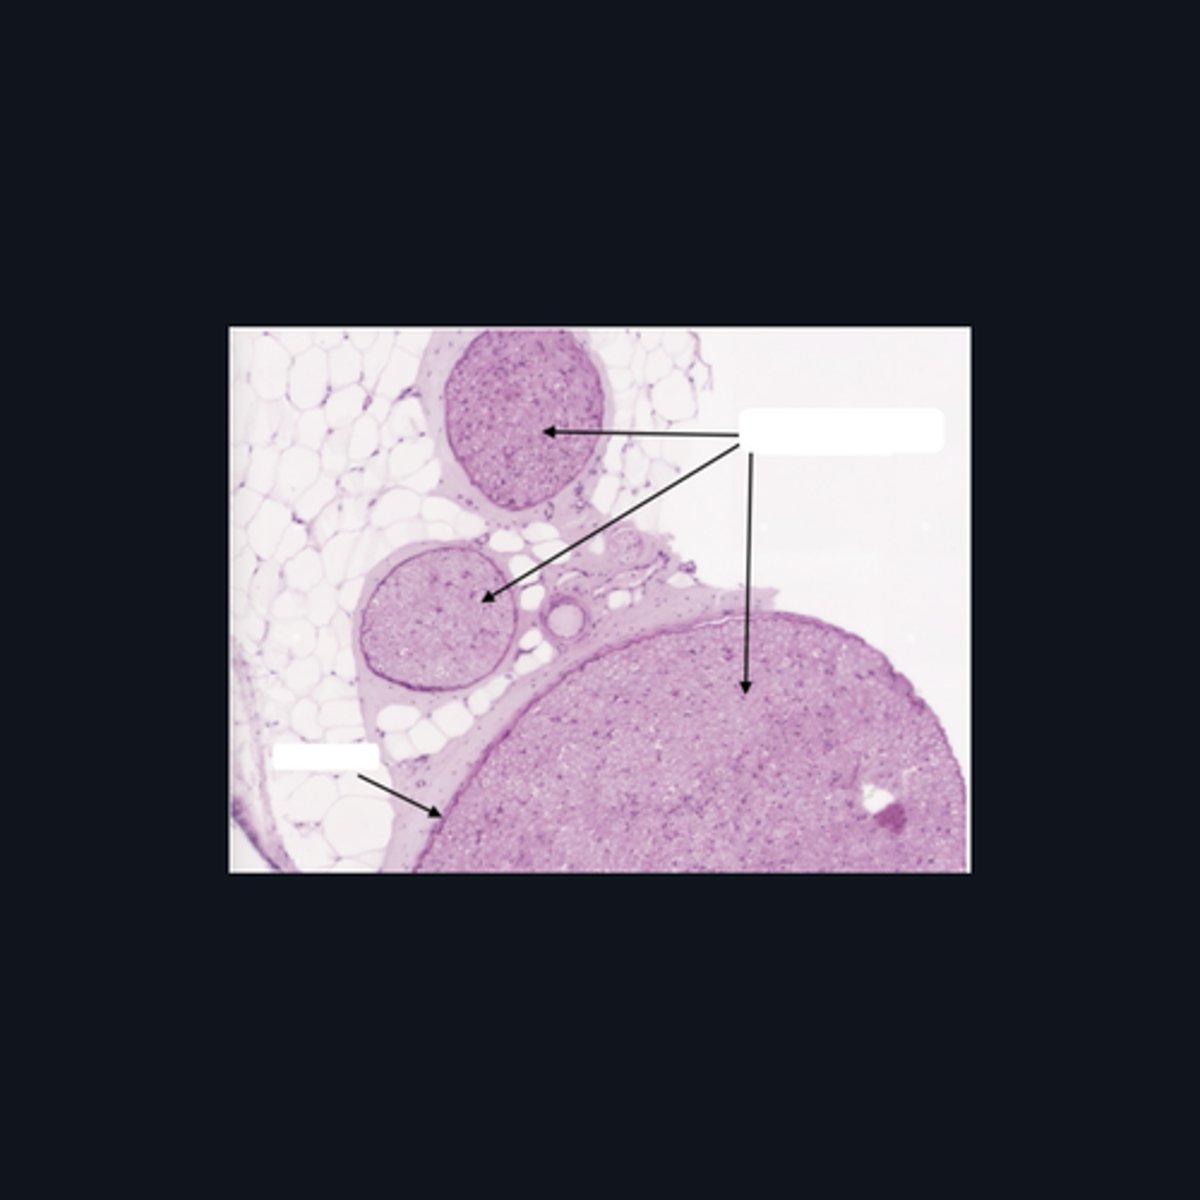

Dorsal root ganglion and nervous tissue

Identify the specific structure given in the image, as well as the type of tissue predominating in the structure.

(top to bottom)

Somatic sensory neurons

Capsule

Identify the structures of the dorsal root ganglion. Be as specific as possible.

(top to bottom)

Cell body

Satellite cell

Nucleus

Nucleolus

Nerve fibers

Identify the parts of the spinal ganglion in high magnification.

False, pseudounipolar

T or F: The neurons that congregate in this structure is multipolar.

(bottom to top)

Capsule

Ganglion Cell

Satellite cell

Nerve fibers

Nucleolus

Nucleus

Nissl Granules

Identify the structures of a sympathetic ganglion.

Multipolar, autonomic motor neurons

What kind of motor neurons are present in this structure?

Dense Irregular Connective Tissue

What kind of tissue is the capsule of a spinal ganglion made up of? Be specific.